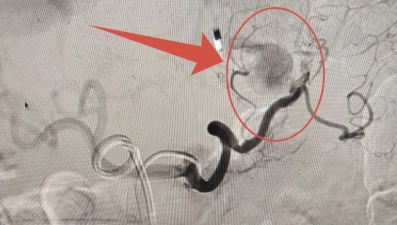

«У мужчины были повторяющиеся эпизоды внутреннего кровотечения. Углубленная диагностика обнаружила причину – две аневризмы на артериях селезёнки и желудка. К лечению пациента подключились эндоваскулярные хирурги. В ангиохирургической операционной под рентгенконтролем обе аневризмы были выключены из кровотока», - рассказали в больнице.

Успешную операцию по эмболизации аневризм провёл врач отделения рентгенхирургических методов диагностики и лечения Владимир Анисимов.